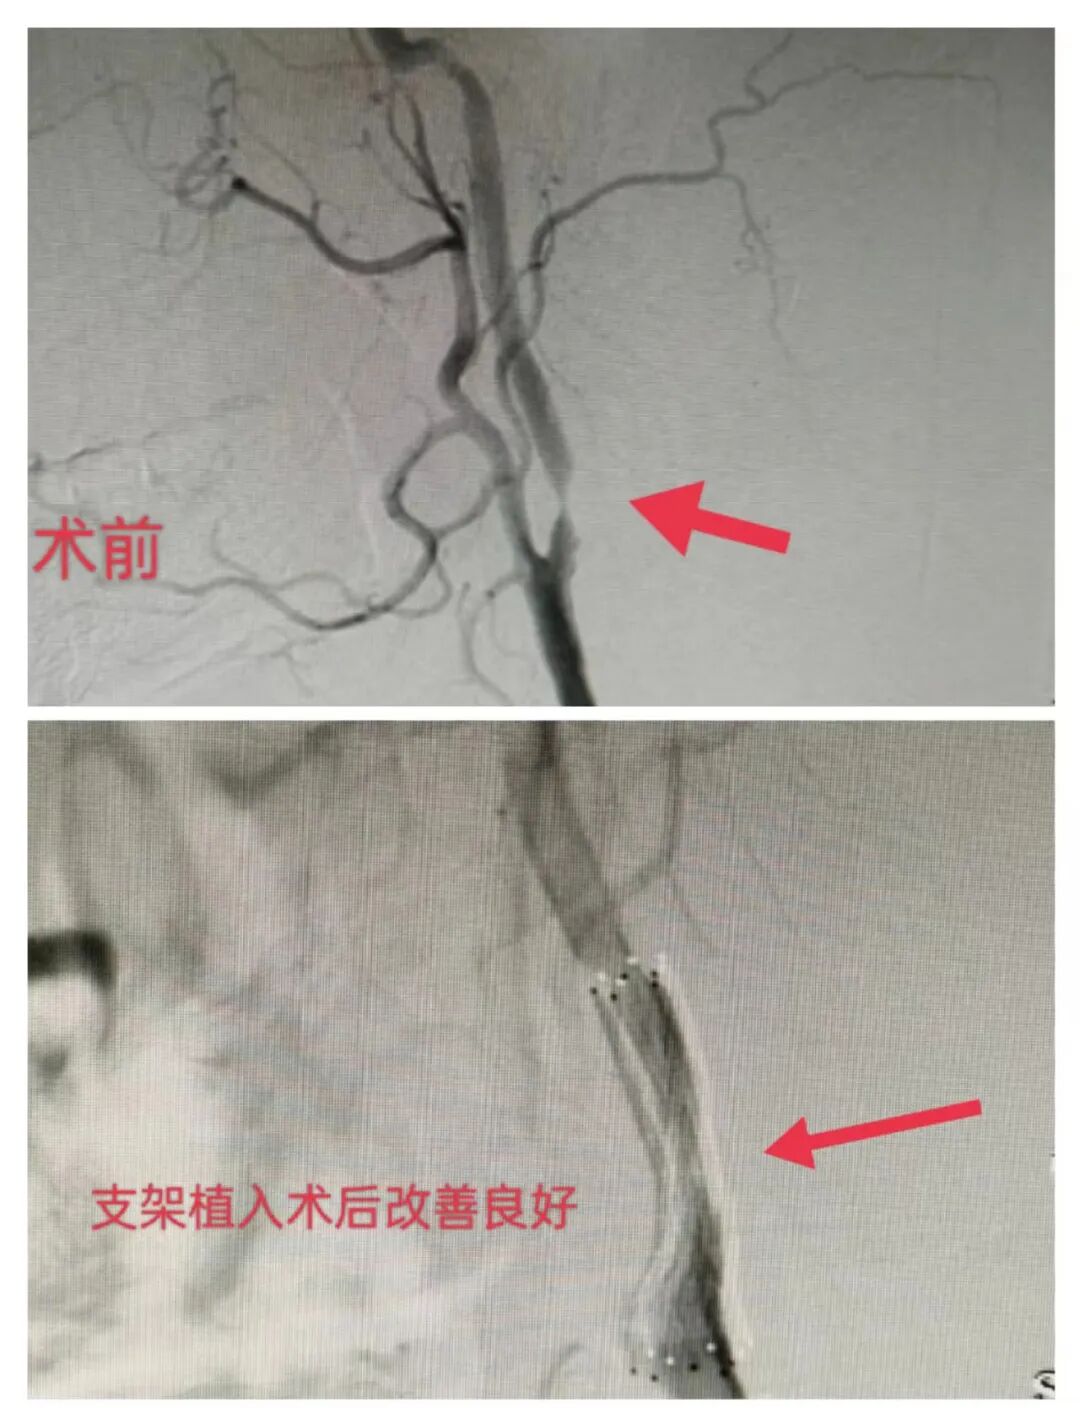

德州联合医院成功实施首例脑血管介入支架成形术

沧州市中心医院 神经内四科 写美篇4,支架成形术:可使狭窄的局部脑